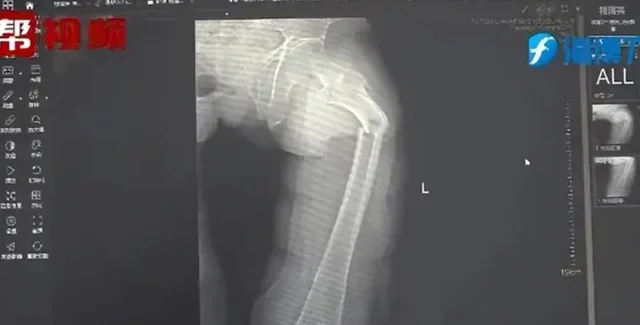

Рентген показал перелом бедренной кости у господина Е. | Фото: Oddity Central

Рентген показал, что у господина Е перелом бедренной кости. Его история о кашле не соответствовала никаким физическим травмам. Доктор Чжун и его команда решили провести дополнительное обследование. Они расспросили пациента о его общем состоянии здоровья, пищевых привычках и образе жизни, а также провели тест на плотность костной ткани, который продемонстрировал тревожные результаты. Показатели 35-летнего мужчины соответствовали норме 80-летнего. Эти результаты являются необычными даже для современных малоподвижных людей.